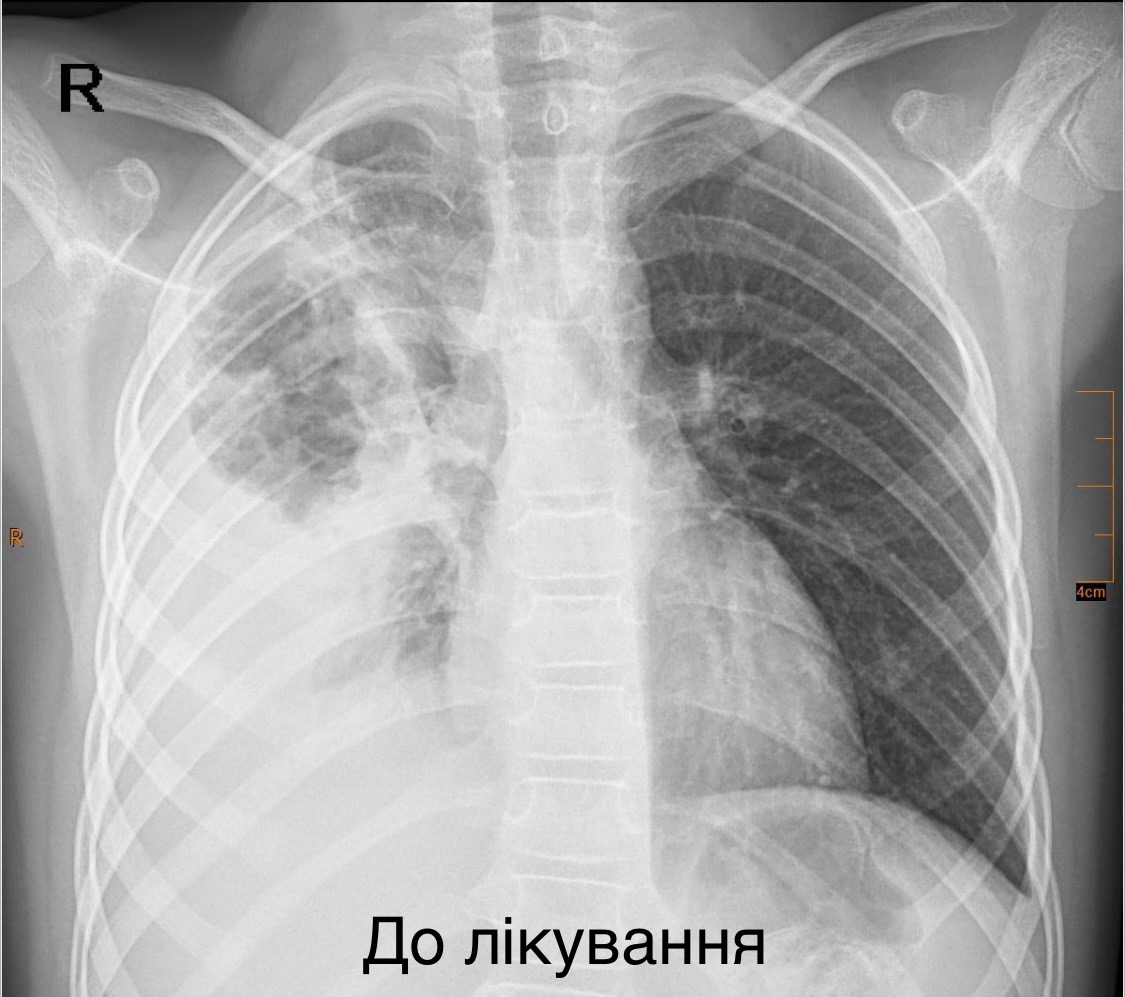

Команда торакальних хірургів Центру дитячої медицини врятували 7-річну дівчинку з важкою деструктивною пневмонією правої легені. Про цей випадок розповіли в медзакладі “Охматдит”.

Дитину екстренно доставили каретою швидкої допомоги до нашої лікарні “Охматдит”. Дівчинка була у важкому стані, мала високу температуру тіла, задишку, низьку сатурацію кисню у крові. Дитину одразу госпіталізували у Клініку торакальної хірургії.

Лікарі розпочали інтенсивну терапію – призначили два потужні антибіотики, щоб зупинити інфекцію, інфузійну та кисневу терапію. Але головним етапом лікування стала торакоскопічна операція – малоінвазивне втручання, яке виконала команда торакальних хірургів.

“Лише через 2 розрізи розміром до 1 см ми дісталися до ураженої легені, усунули гнійно-некротичні вогнища і зберегли легеню”, – наголосив торакальний хірург Олександр Колодій.